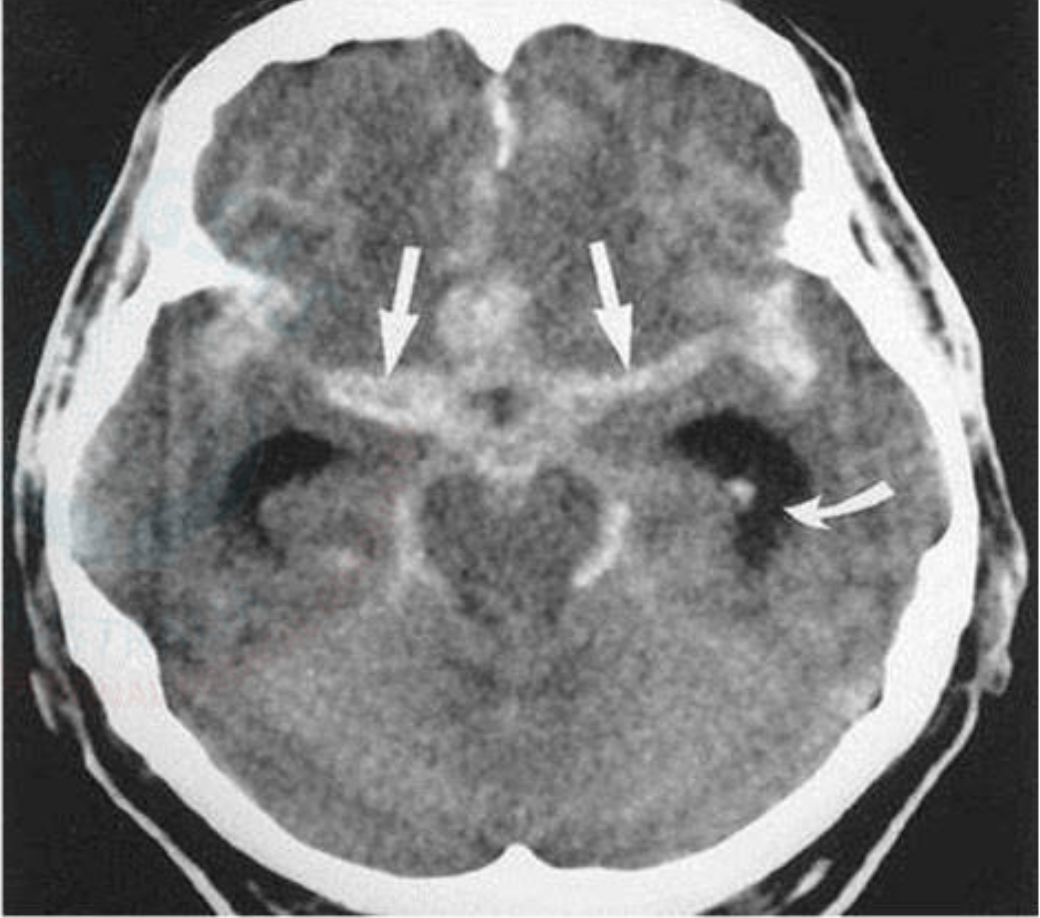

Headache: Subarachnoid Hemorrhage CT Imagen

Areas of hyper density within the cisterns and sulci

Dx: 1) CT Head – investigation of

choice

2) Lumbar puncture is used if CT scan is

negative – Homogenous blood staining of CSF

and Xanthochromia are diagnostic of SAH